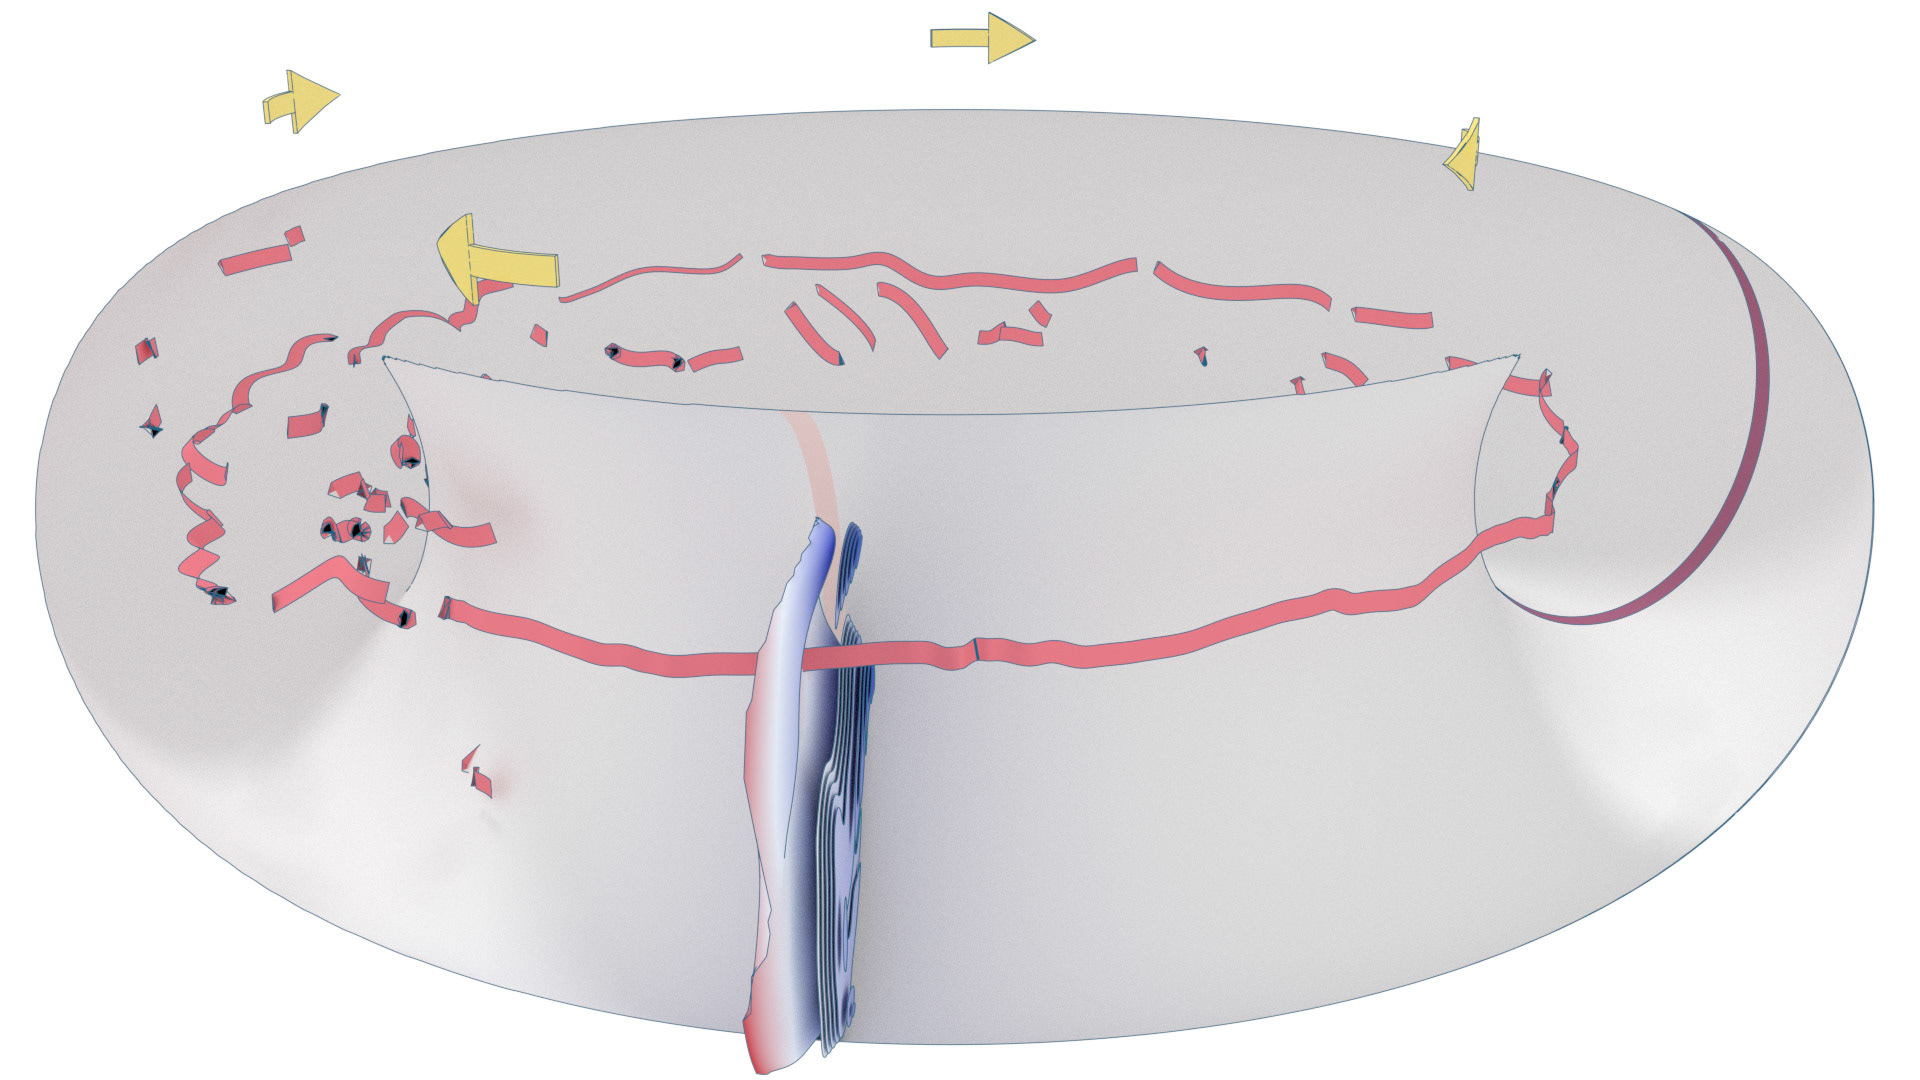

An ongoing collaboration with the Biomedical Simulation Lab (BSL), University of Toronto. In my role, I develop concept sketches and renderings that are then implemented algorithmically. The overall approach is to show turbulent flow visualizations without animation my mapping the transitions among states to carousel that corresponds to the cardiac cycle.